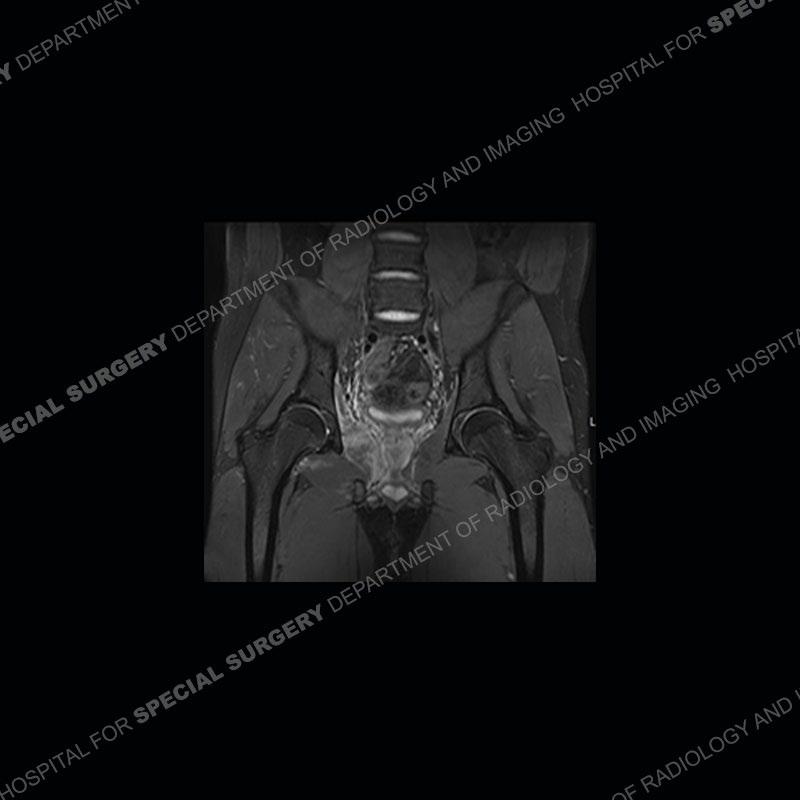

Radiographs did not demonstrate any clear abnormality. The MRI shows markedly abnormal signal of the right superior pubic ramus and abnormal signal/”mass” extending into the adjacent soft tissue. The inferior articular surface of the ramus showed what was thought to be bony destruction. CT examination shows a destructive process of the right superior pubic ramus.

Subsequent MRI in a very short time interval shows markedly increased abnormality of the ramus and increased edema and “mass” of the soft tissue. Post contrast imaging shows multiple, rim enhancing collections of the soft tissue and similar albeit less conspicuous enhancing collection of the ramus.